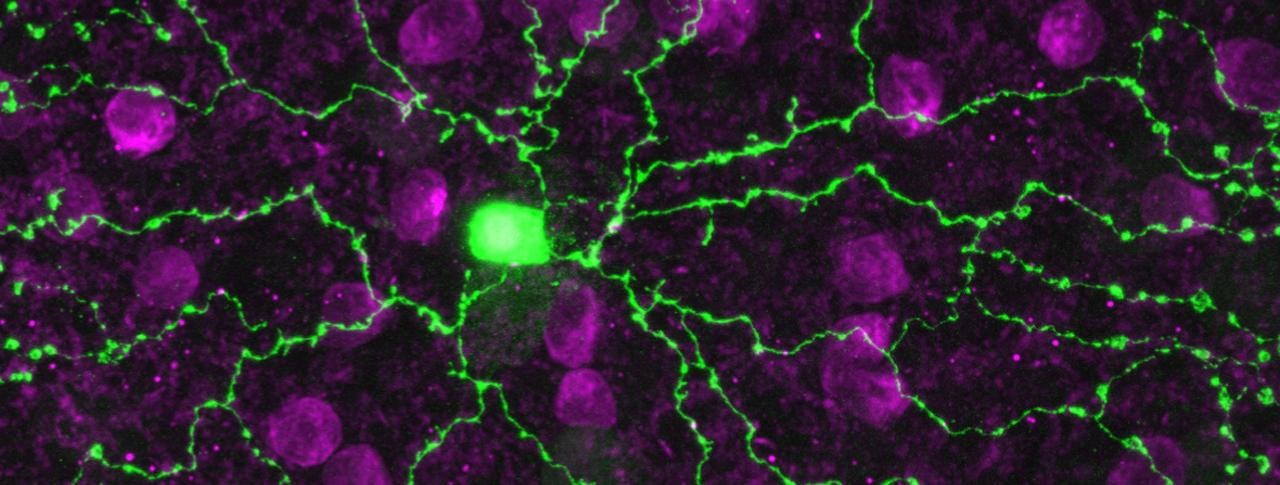

Enter Botond Roska, a neurobiologist and principal investigator at the Novartis-affiliated Friedrich Miescher Institute for Biomedical Research. His group discovered that FRMD7 mutations wreak havoc by sabotaging exquisite retinal cells called starbursts (above). Specifically, the mutations interfere with the cells’ ability to decode sideways movement. This finding, published in Neuron, provides critical insight for understanding and potentially treating nystagmus.

It’s easy to see how the starburst cell got its name. Many arms radiate from a central body. And these projections play a critical function, connecting with other cells in a neural circuit that processes vision. Starburst cells are known to be essential for deciphering and transmitting information about movement in all directions. Given this role, it wasn’t surprising for starburst cells to be implicated in nystagmus. But, there was something peculiar about the starburst cells in the genetically-modified mice.

Main image: This starburst cell (in green) looks healthy, but its faulty cellular contacts underlie the debilitating retinal disease nystagmus. Image by Botond Roska/FMI